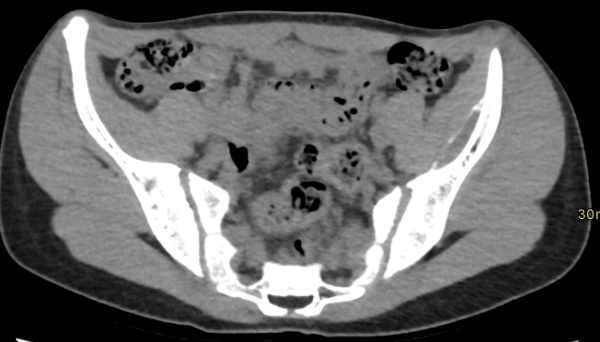

Cortes axiales de TC de pelvis, en ventana de partes blandas (Imagen 6) y ósea (Imagen 7). Lesión lentiforme subperióstica iliaca izquierda, con calcificación periférica.

Colección hemática entre el periostio y la cortical, generalmente post traumática. Se presenta como una lesión lentiforme adosada al hueso, con niveles líquido-líquido en RM y sin realce significativo tras contraste. Puede asociarse a calcificación periférica en TC. Los hallazgos descritos y el antecedente clínico son concordantes con este diagnóstico.